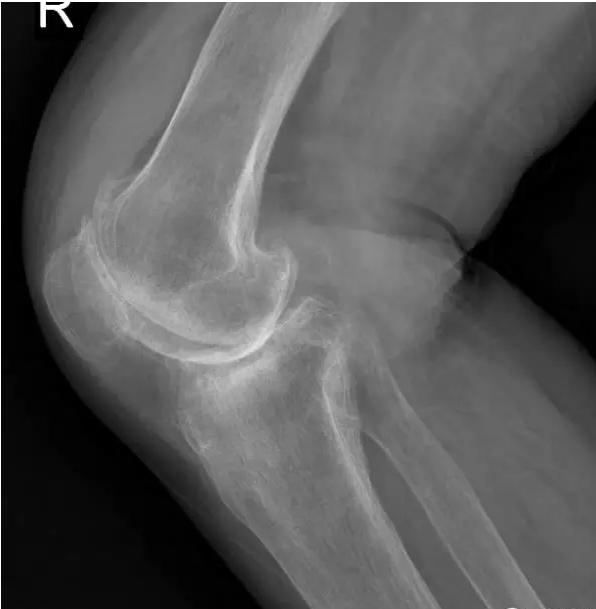

中期:骨关节炎表现为膝关节持续性疼痛,活动后或上下楼梯时加重,压痛明显; X线片上可见增生的骨赘,关节间隙出现狭窄,多为不对称性狭窄。

膝关节不均匀沉降术后患者X线片(下图)